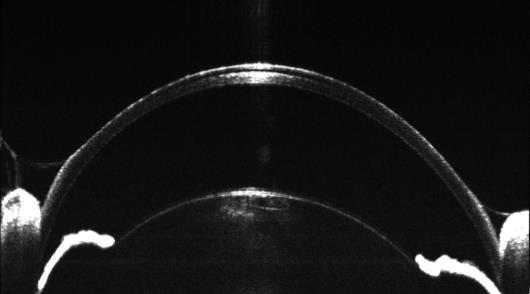

應(yīng)用:眼前節(jié)OCT成像及定量分析

眼前節(jié)OCT適用于糖尿病眼病、白內(nèi)障、青光眼等眼科病的檢查??蓱?yīng)用于角膜、房角、晶狀 體等眼前節(jié)結(jié)構(gòu)的生物測(cè)量和眼病研究。

眼前節(jié),角膜及房角OCT